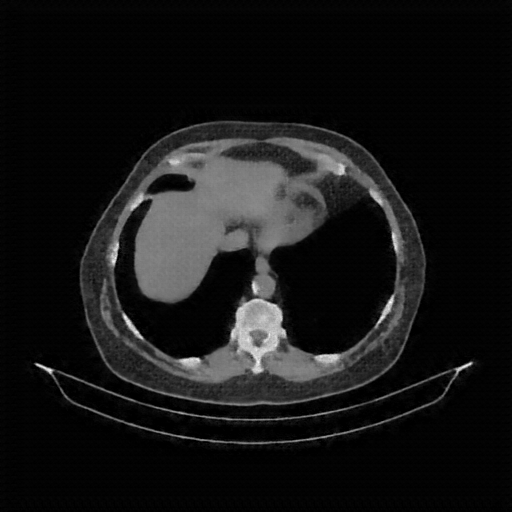

Reconstructed NATIVE CT scan (cycle consistency)

Full window (WL 1023.5, WW 4095 β†’ Low βˆ’1024, High +3071)

Actual HU range: [-1024.0, 783.0]

Lung window (WL -600, WW 1500 β†’ Low βˆ’1350, High +150)

Actual HU range: [-1281.6, 150.0]

Mediastinum window (WL 40, WW 400 β†’ Low βˆ’160, High +240)

Actual HU range: [-160.0, 240.0]